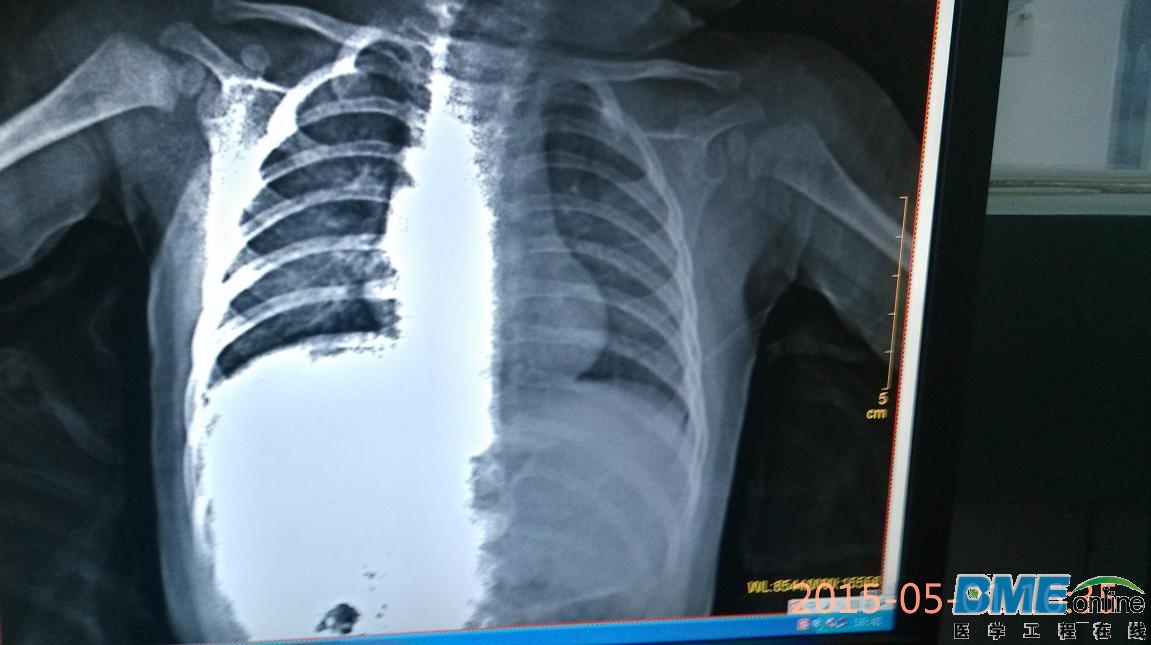

关于X光成像有前辈遇到这种问题吗

蓝韵晶睿2200S成像不均问题,另求该设备技术资料,先行谢过。。